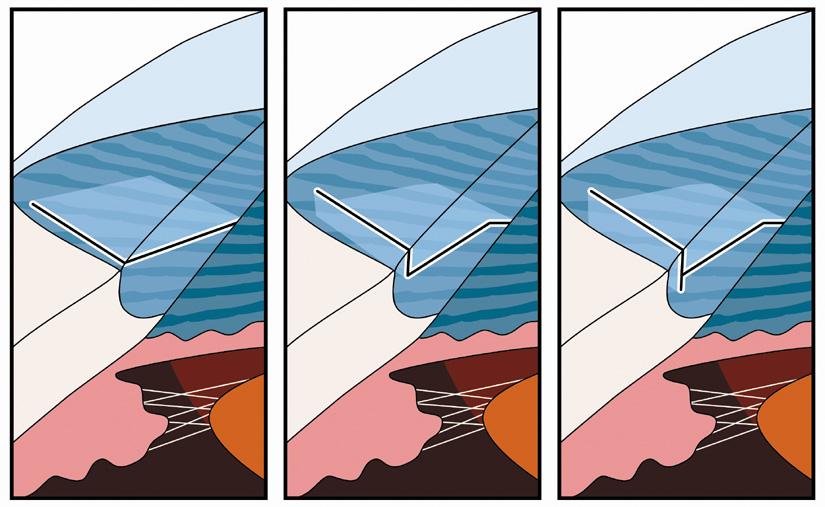

SURGICAL TECHNIQUE Some surgeons prefer to perform LRIs at the conclusion of surgery in the

event that a complication occurs necessitating a modification to the

phaco incision. For routine cases, however, our preference is to place

these relaxing incisions at the outset of surgery in order to minimize

epithelial disruption. The one exception to this rule occurs in the

case of high ATR astigmatism wherein the nomogram calls for a temporal

arcuate incision greater than 40 degrees of arc. Because the temporal

arc will be superimposed upon the phaco incision, if it is extended

to its full arc length at the start of surgery, significant gaping and

edema may result secondary to intraoperative wound manipulation. In this

setting, the temporal incision is first made by creating a two-plane

grooved phaco incision (at 600 micron depth). Following IOL

implantation and prior to viscoelastic removal, while the globe is

still firm, the relaxing incision is extended to its full arc length as

dictated by the nomogram. When an LRI is superimposed upon the phaco

tunnel, the keratome entry is first accomplished by pressing the bottom

surface of the keratome blade downward upon the outer or posterior

edge of the LRI. The keratome is then advanced into the LRI at an iris-parallel

plane. This angulation will promote a dissection that takes

place at midstromal depth, which will help assure adequate tunnel length